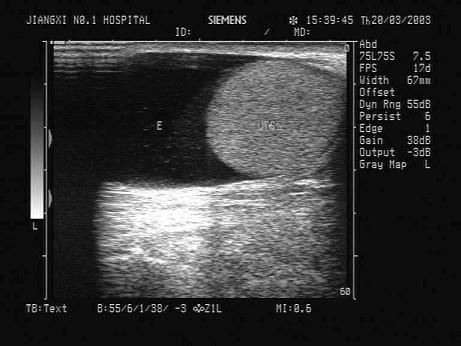

问题 根据超声声像图,最可能的诊断为?(?)

选项 A.睾丸鞘膜积液 B.精索鞘膜积液 C.睾丸囊肿 D.交通性鞘膜积液 E.附睾头囊肿

答案 A